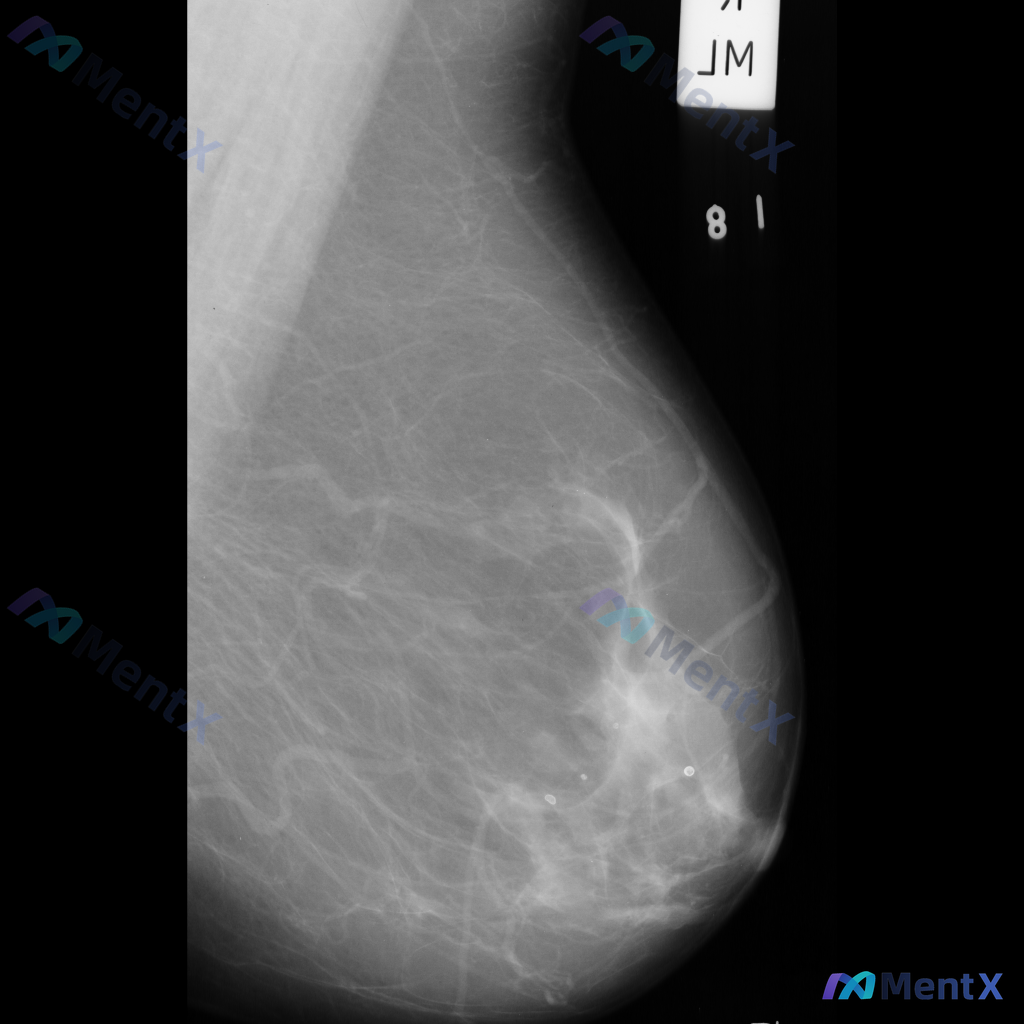

整理到一组乳腺钼靶影像的资料,分享给大家讨论: - 背景:不均匀致密型乳腺(BI-RADS C类) - 主要异常: 1. 乳腺下象限靠近乳头乳晕区,见两个大小不一的圆形/卵圆形高密度影,还有一个较小的类圆形高密度影,密度高于周围腺体,边缘相对清晰但略显模糊; 2. 上述高密度影周围的乳腺下象限,腺体...

整理到一份乳腺钼靶的影像资料,想和大家讨论一下: - 钼靶所见:左侧乳腺中央偏下区域存在局限性结构扭曲,表现为纤维腺体组织排列紊乱、牵拉;未见明确的肿块或钙化灶。 - 背景:乳腺密度较高,属于不均匀致密型或极度致密型(ACR B或C型)。 目前这种结构扭曲的表现,大家会先往哪个方向考虑?下一步的评估...